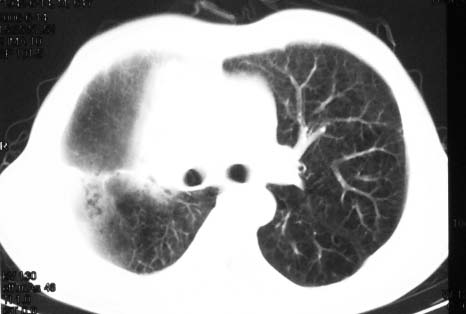

影象表现:右肺上叶大片状、网格状及索条致密影,蜂窝影,其内参杂斑点状小结节,密度不均匀,内见含气支气管像,纵隔内见肿大淋巴结.

抗感染病变无明显改善,右上叶大片状增弥不均匀病灶,夹杂网状及支气管充气像,肺门纵隔淋巴结肿大,右侧胸腔积液。考虑1混合感染伴肺间质改变[警惕特殊感染,如真菌]。2细支气管肺泡癌。建议结合临床及进一步检查[如痰,胸水脱落细胞检查及支气管镜检灌洗或穿刺活检

影象表现:右肺上叶大片状、网格状及索条致密影,蜂窝影,其内参杂斑点状小结节,密度不均匀,内见枯枝样含气支气管像,纵隔内见肿大淋巴结.胸膜广泛增厚,前胸壁似受累.少量胸腔积液.纵隔内淋巴结的直径>1.5cm.右侧胸廓体积缩小.考虑:1 肺结核合并间质纤维化 2 细支气管肺泡癌

右肺上叶大片状、网格状及索条致密影,蜂窝影,其内参杂斑点状小结节,密度不均匀,内见枯枝样含气支气管像,纵隔内见肿大淋巴结.胸膜广泛增厚,前胸壁受累增厚.少量胸腔积液.纵隔内淋巴结的直径>1.5cm.右侧胸廓体积缩小.考虑: 细支气管肺泡癌并肺内癌性淋巴管炎。